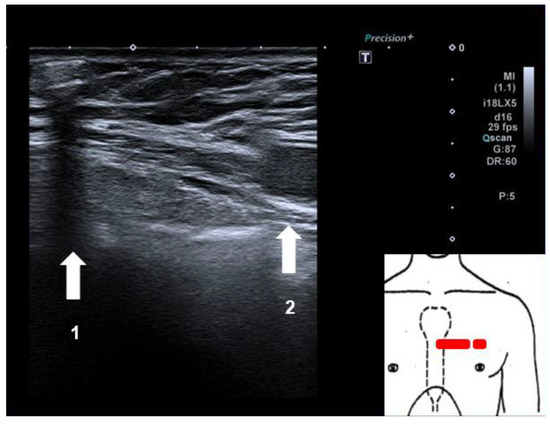

Successful Implantation of an Implantable Loop Recorder in a Patient with Bilateral Silicone Breast Implants Leading to a Diagnosis Explaining Repeated Syncopal Events

by Beeler Remo, Gujer Samuel, Lehmann Dietrich and Kaeslin Thomas

Cited by 1

We report the case of a 54-year-old patient with bilateral silicone breast implants in whom successful implantation of a subcutaneous loop recorder led to the diagnosis that explained her repeated syncopal events. Full article